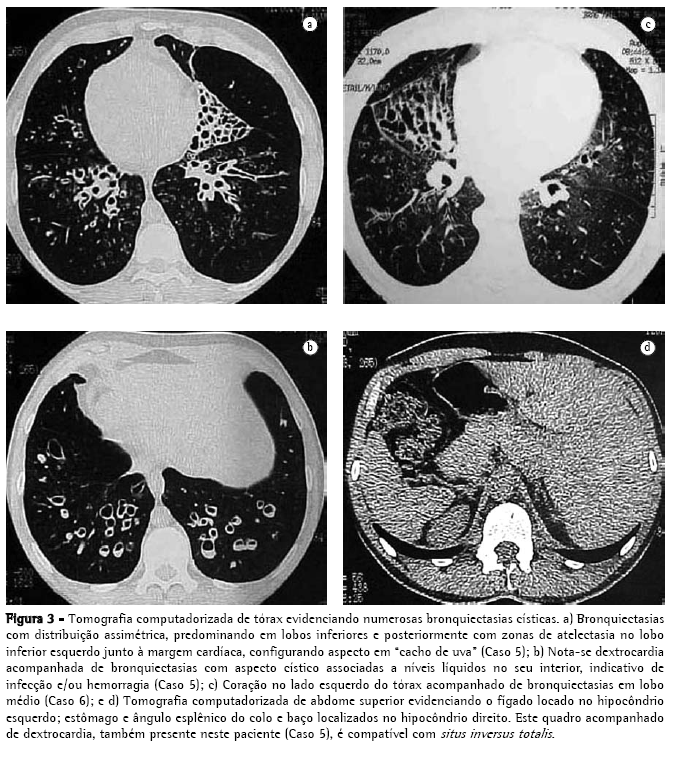

Nos quatro primeiros casos da série, foram realizadas broncografias em dois períodos: primeiro de um lado e, após um intervalo aproximado de 30 dias, do outro lado. Nos dois últimos casos, as broncografias foram substituídas pela tomografia axial computadorizada de alta resolução. Ambos os exames mostraram diversos tipos de bronquiectasias (cilíndricas, císticas e varicosas) que se localizavam principalmente nos lobos inferiores, no lobo médio esquerdo e na língula direita devido ao situs inversus (Figuras 2, 3a, 3b e 3c).

Os cinco primeiros casos da série tinham dextrocardia, sendo que o Caso 5 apresentava também situs inversus totalis (Figura 3d). O Caso 6 foi o único que apresentou levocardia. Todos os seis pacientes apresentavam roncos e estertores audíveis nas bases pulmonares, eram física e intelectualmente desenvolvidos e ocupacionalmente ativos (Tabela 1).

Apesar da sua aceitação universal como o melhor método para o diagnóstico e avaliação cirúrgica das bronquiectasias, a broncografia descrita inicialmente por Sicard e Forestier, em 1922, tem sido menos utilizada ultimamente. Isso se deve a vários fatores: reação alérgica ao contraste; broncoespasmo (o procedimento provoca extremo desconforto no paciente); realização em um pulmão de cada vez (o estudo do outro pulmão só pode ser realizado após duas a quatro semanas de intervalo) e dificuldade de interpretação por radiologistas menos experientes. Porém, o fator mais importante foi o advento da tomografia computadorizada na década de 80, a qual constitui, hoje, o método de escolha para o estudo das bronquiectasias(19,20) (Figuras 3a, 3b e 3c).